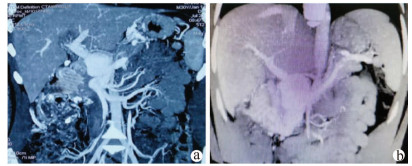

Massive hemorrhage caused by total gastrointestinal varices and recurrent heterotopic varices due to portal vein tumor: A case report

Qin LIU, Heye LIANG

2021, 37(10): 2414-2416. DOI: 10.3969/j.issn.1001-5256.2021.10.032

Abstract(752) HTML (344) PDF (3571KB)(53)

Abstract: